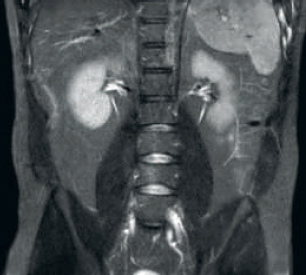

dStream RF receive technology digitizes the MR signal directly in the RF coil, resulting in an increase of up to 40% more SNR* throughout the whole image volume.